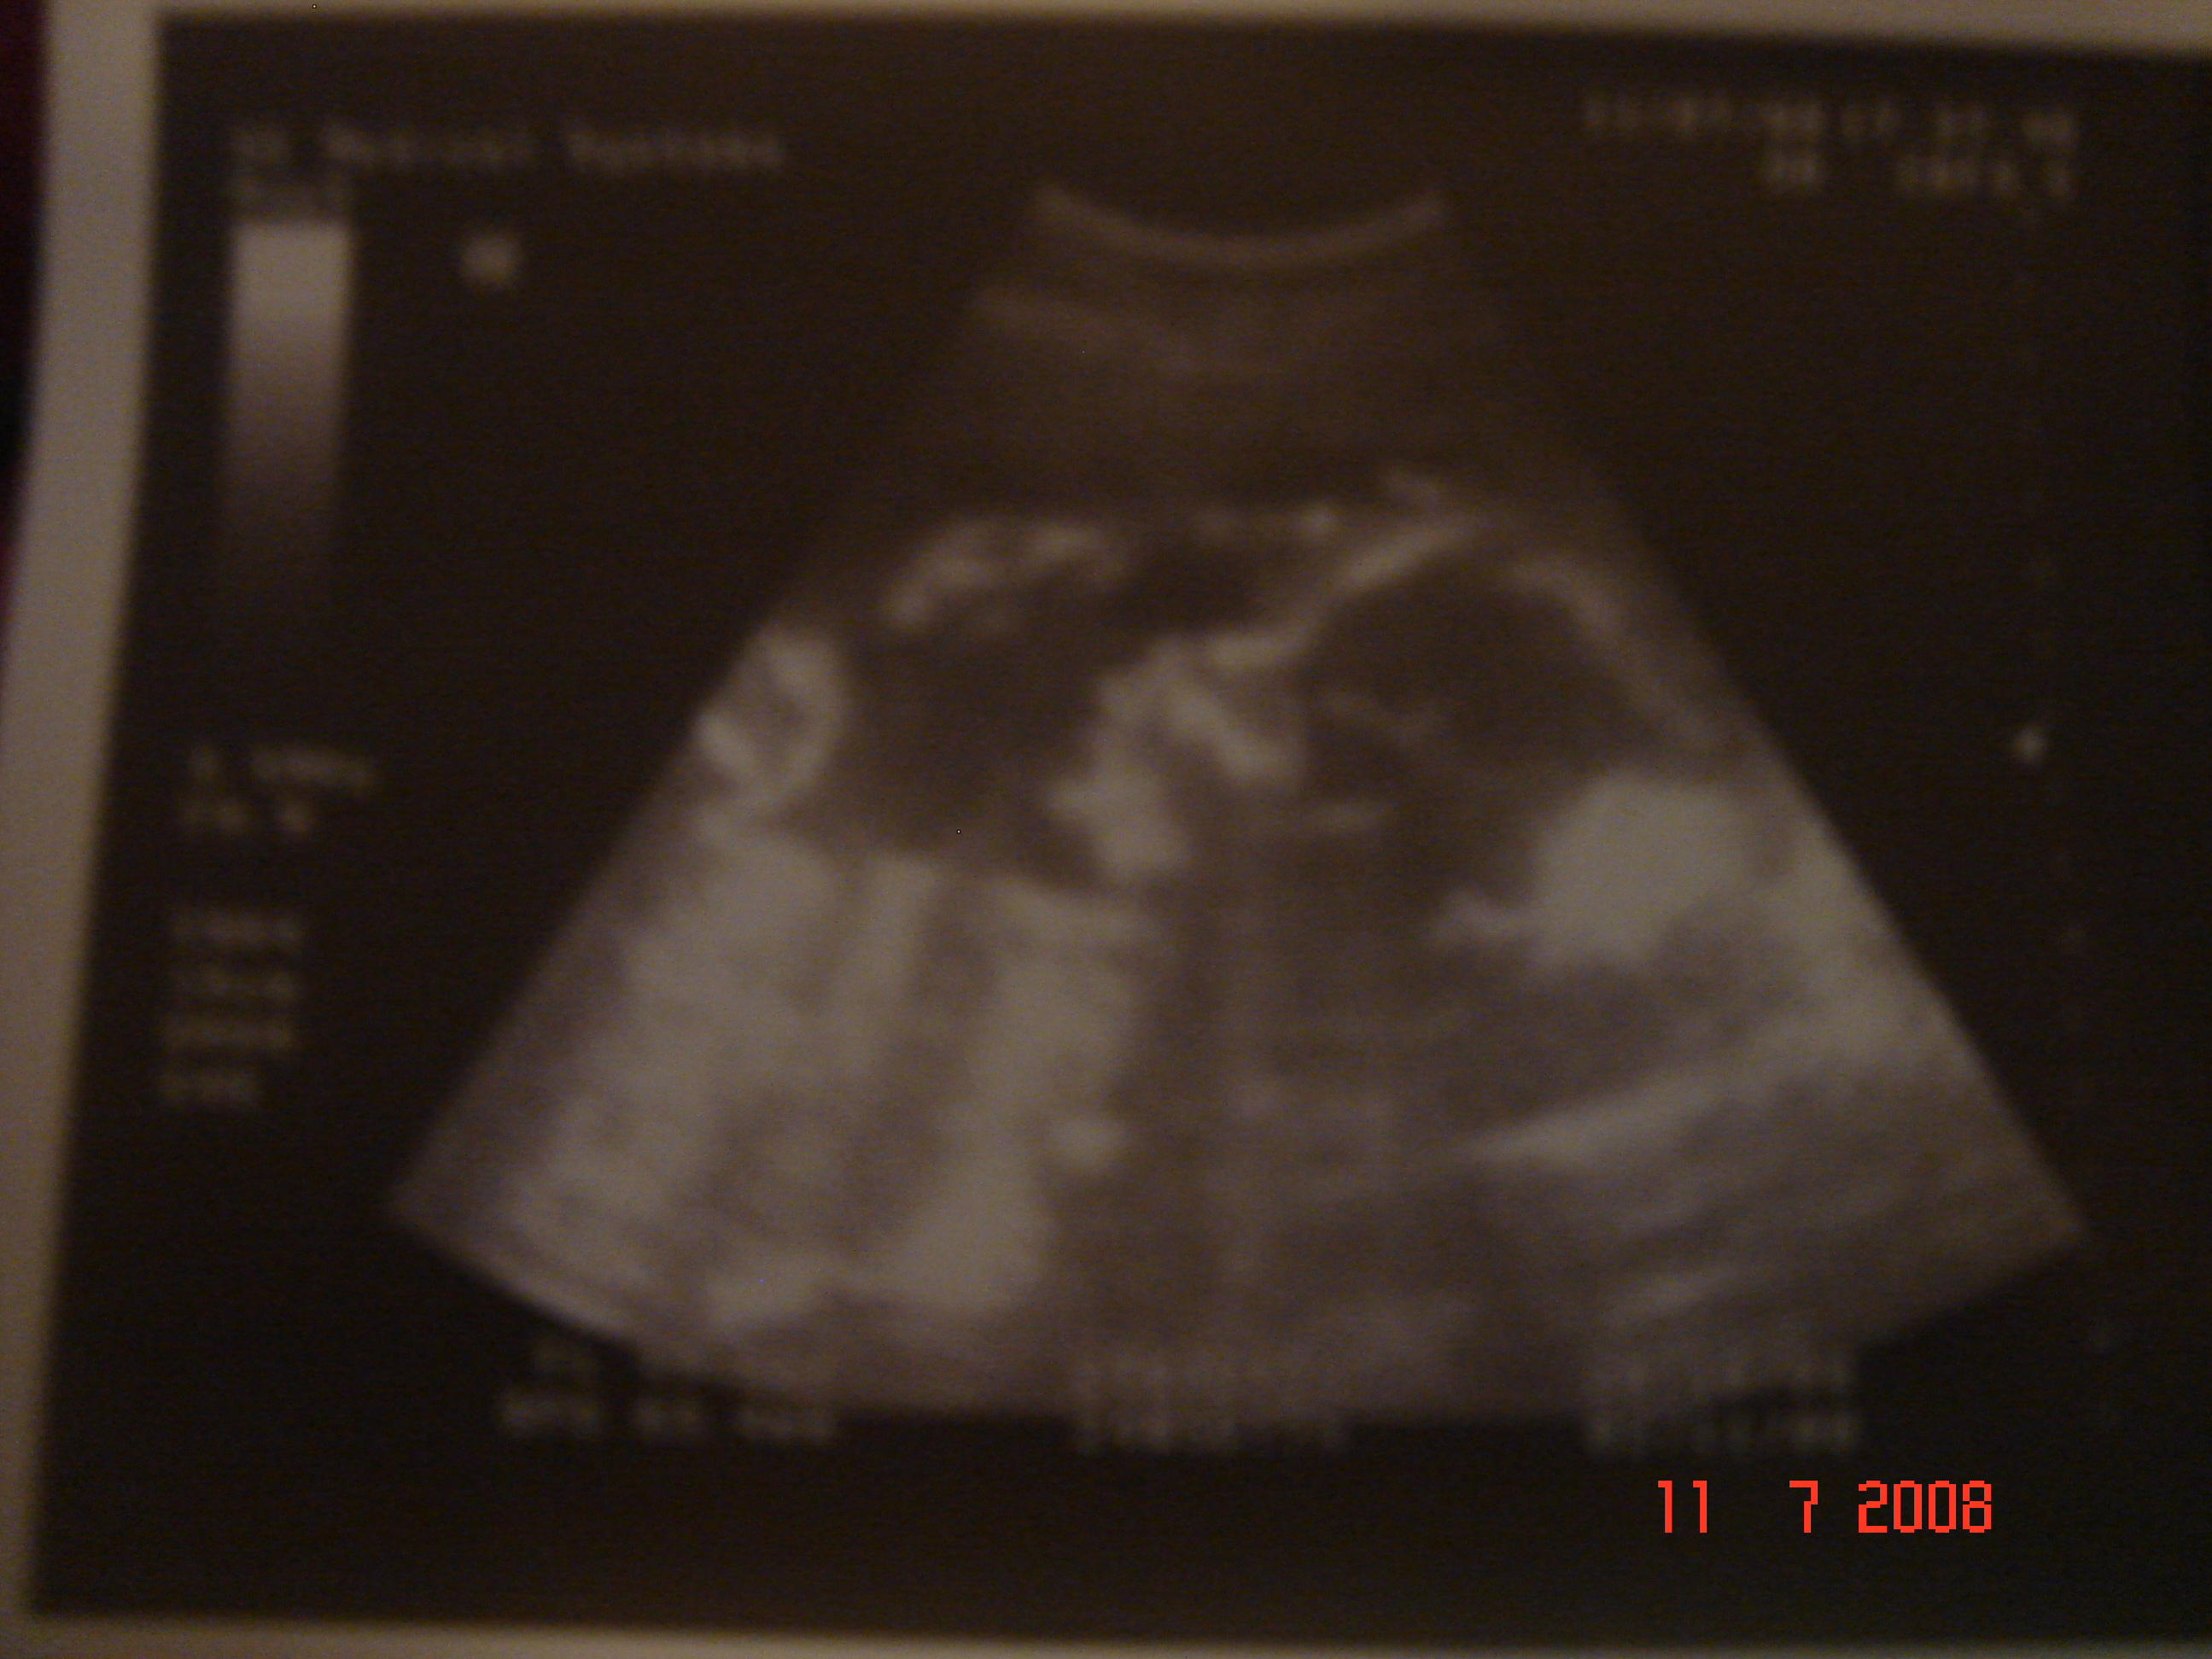

Smerfik jest smerfikiem nie smerfetką:-p zdrowiótki i bardzo aktywny.

Mam delikatne rozwarcie zew. ale ile to nie wiem w karcie zawsze przy szyjce miałam pisane 1,0 teraz m am 1,5:sorry::sorry: ale wew OK. i miałam usg długosci szyjki wyszło 37,4mm a na początku było 41,7mm czyli jakby skrócona ale nic o tym niewspomniała. Po zatym Ok i mam tak dalej trzymac. Aaaaa z USG mój ludek wychodzi na 25 tyg,3 dni. ale ja nie biore tego pod uwagę

a to profil Samusia

Załączniki

• DSC03443.jpg

DSC03443.jpg

325,6 KB · Wyświetleń: 54